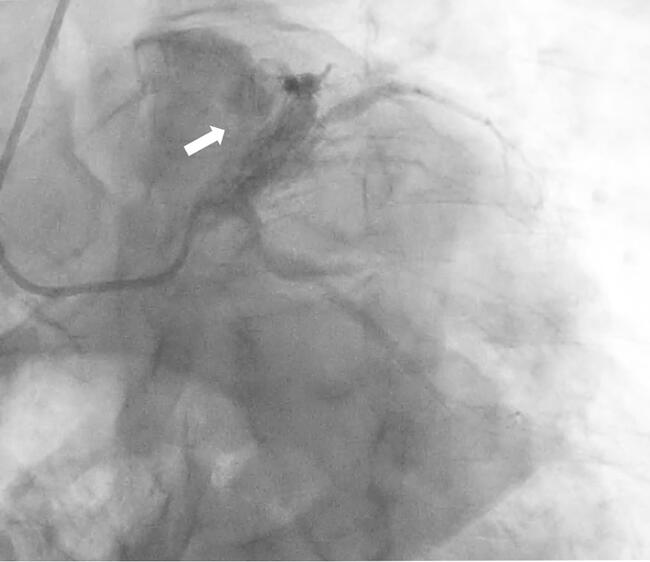

An 80-year-old male with hypertension and hyperlipidemia presented with chest discomfort and dyspnea. Initial investigations, including electrocardiogram and labs, were unremarkable. However, the patient had a high outpatient coronary artery calcium score which prompted further workup. Left heart catheterization showed a large coronary cameral fistula with multiple connections from the proximal left anterior descending artery to the right ventricular outflow tract and main pulmonary artery, with angiographic evidence of coronary steal (Figure 1, arrow). Right heart catheterization showed stable hemodynamics with a Qp:Qs ratio of 1.0 and no significant oxygen saturation step-up, indicating absence of a hemodynamically significant shunt. Given that the patient has lived 80 years with this congenital condition without right atrial or right ventricular enlargement or significant pulmonary hypertension, the decision was made to manage medically with a beta blocker in addition to continuing aspirin and statin. Timely identification and individualized management of coronary cameral fistulae are essential. Percutaneous closure is first-line for accessible, symptomatic fistulas. Conservative management remains appropriate in asymptomatic, hemodynamically insignificant cases, with close imaging and clinical follow-up as per American College of Cardiology guidelines.